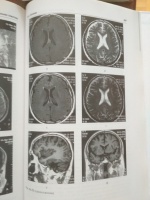

Прилагаю фотографии для ознакомления.

Замечательная доступно написанная монография, касающаяся самой актуальной для нейрохирургии проблемы - ЧМТ. Книга богато иллюстрирована рисунками, КТ, МРТ и т.п., имеется вкладка с цветными фотографиями. Удобный формат, мелованная бумага, качественная печать.